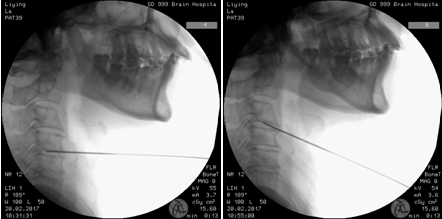

完善相关术前准备后,骨科王延斌主任及其团队在局麻下为赖奶奶进行“C3/4、4/5、5/6椎间盘射频热凝术”。术后赖奶奶的头晕症状缓解遂出院。

术中透视

射频热凝靶点治疗是在C型X光机下准确定位,数字减影下时时监测,导航系统的精确定位下直接把突出部位的髓核变性、凝固;收缩减小体积,解除压迫。不伤及正常的髓核组织,同时修补了纤维环的破裂、灭活了盘内新生病变超敏的神经末梢,直接阻断了髓核液中糖蛋白和β蛋白的释放,温热效应对损伤的纤维环、水肿的神经根、椎管内的炎性反应起到良好的治疗作用。

在射频热凝治疗过程中,在C臂机下进行准确定位,用一根直径只有0.7mm的穿刺针,直接作用在病变的髓核上,进行热凝消融。整个操作,精确,严谨,15-20分钟便可完成整个手术,手术不伤及任何正常组织,对人体无任何副作用,术后有些患者几个小时就可以出院了。